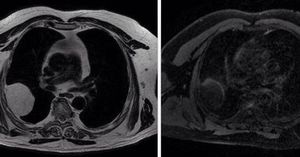

Liposarcoma

Because of the presence of fat, the lesion appears with high signal intensity on T2-weighted image (due to J-coupling effects) and with low signal intensity on fat suppressed T1-weighted image. via MDCT